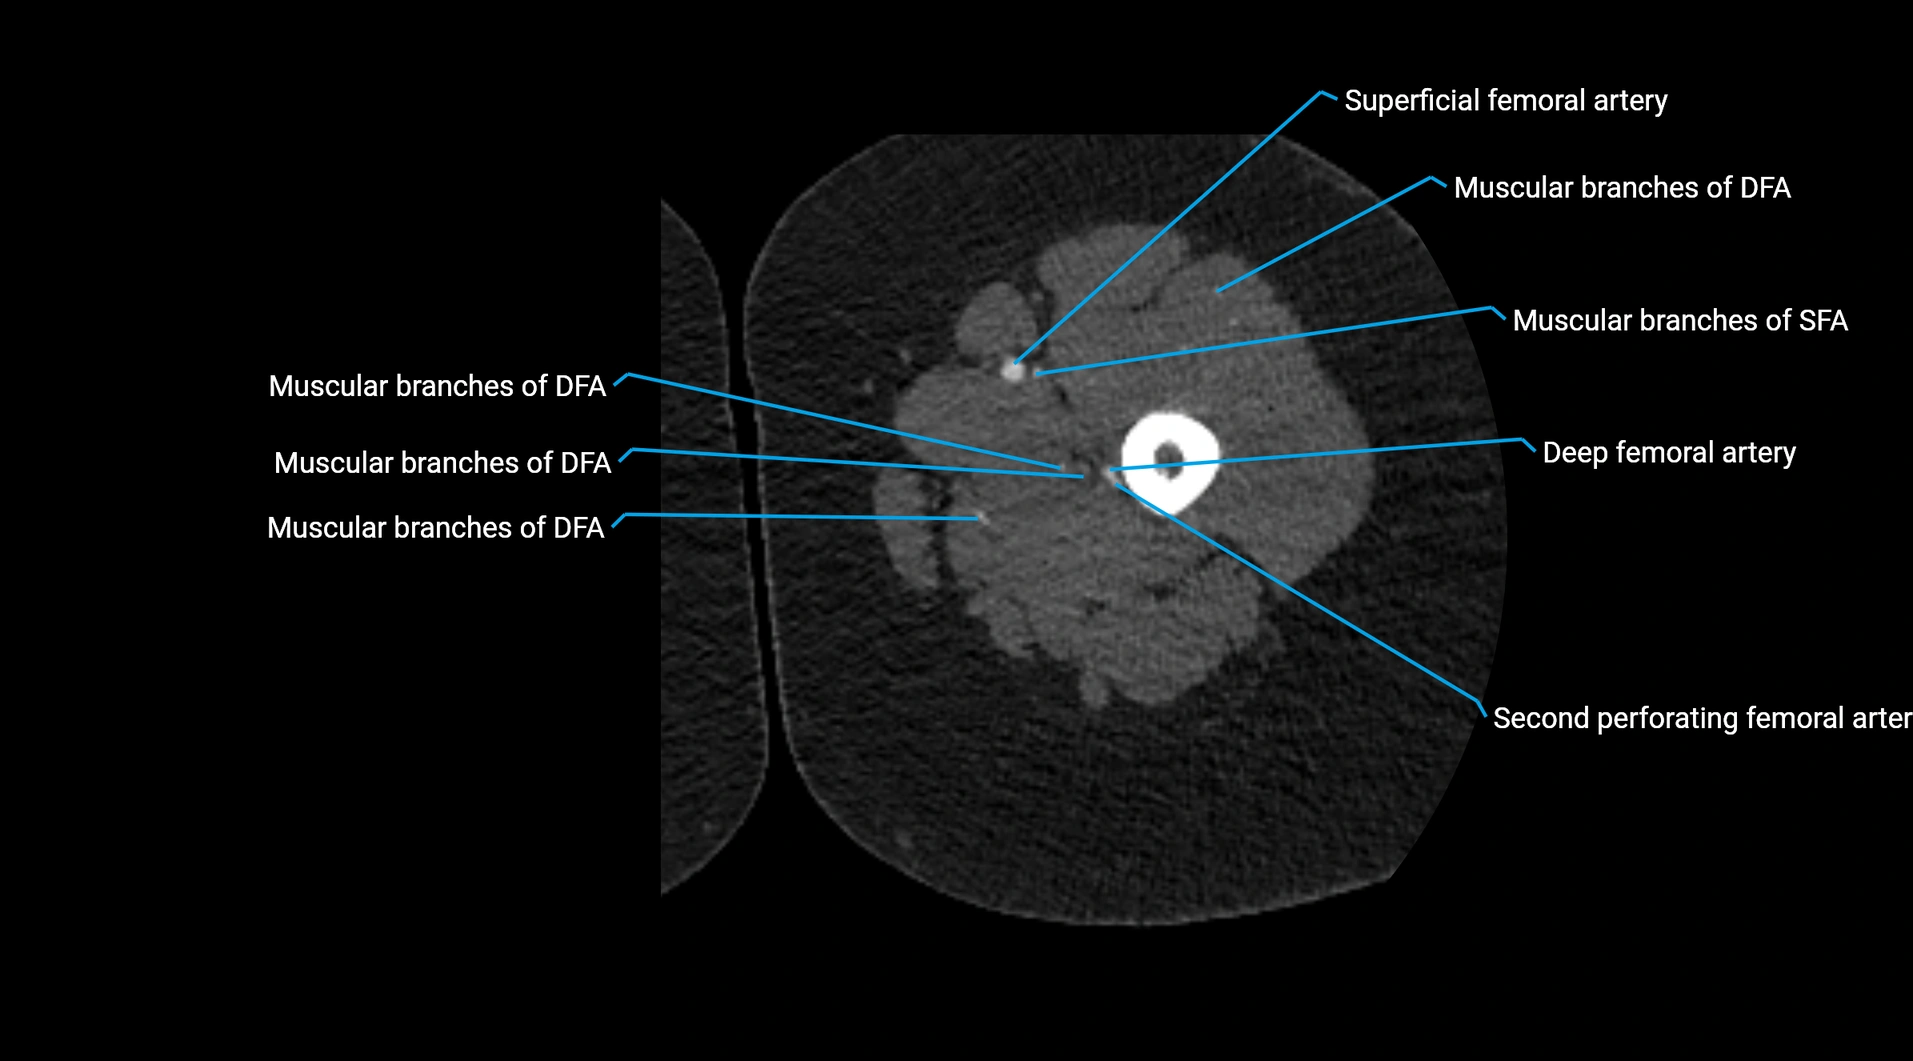

CT images

image

Contrast-enhanced CT (CTA):

• Gold standard for abdominal aortic imaging

• Provides excellent detail of lumen, wall, aneurysm, thrombus, and branch vessels

• Multiplanar and 3D reconstructions help in aneurysm measurement, stent graft planning, and dissection evaluation